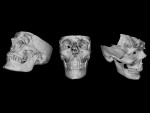

By observing the human representations of Mayan remains, one can notice recurrent characteristics in the craniofacial profile (Figure 1). The face is pulled up giving the skull an ovoid shape. The nose is elongated, and the forehead is flat with a nasofrontal angle so open that the nose seems to be continuous with the top of the skull. These criteria are found in representations of adult men and women as well as children. The reason is simple: The Mayas gave their children, from a very young age, rigid plates to direct cranial growth and provide the head a specific shape.4 This secular tradition is similar to craniofacial orthopedics for purely esthetic purposes. The voluntary deformation of the skull aspect was done for the purpose of ethnicity and individual identity.5 Among the Mayas, beauty consisted of having a furrowing forehead and an ovoid skull.6

In this first workflow, a Mayan skull inspired by their craniofacial plastic criteria will be recreated. First, the acquisition of a skull is made by means of a CBCT (iCat™ FLX V10, Kavo Dental, kavo.com). The result is a DICOM file that contains all the necessary information in the form of pixels in gradual gradation in Hounsfield units. The less luminous pixels correspond to empty spaces like air, while the luminous pixels correspond to hard tissues like bone and teeth. The reconstruction software makes it possible to visualize the result in the form of a 3D object. By choosing the appropriate window, it is possible to hide the soft tissues and let only the mineralized tissues appear. A massive face with a fine resolution is obtained (Figure 3). The result obtained is exported in STL format for easy manipulation with software programs.

In a second step, modifications are made virtually. With a mouse click, the frontal bone may be flattened to lengthen the occipital bone and pull the parietal bones upward, while the cranial volume is maintained equally (Figure 4). All of these changes are made by computer, and the operator is able to view the final result immediately. The third step is to print the object in 3D. The computer project is exported in STL format (Figure 5) to be sent to a 3D printer (Solflex 650, Voco, voco.dental/us). A transparent resin (V-Print ortho, Voco) was used to produce a luminous artifact resembling a crystal skull: a Mayan skull printed in 3D (Figure 6).